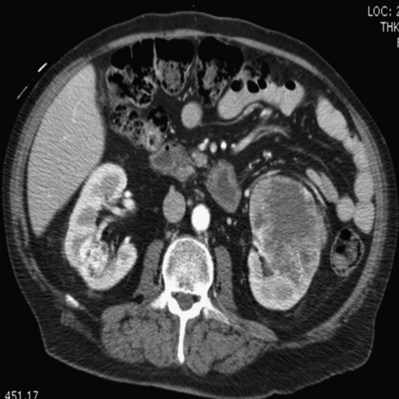

Proposed benefits of preoperative RAE include shrinkage of an arterialized tumor thrombus to ease surgical removal, reduced blood loss, facilitation of dissection due to tissue plane edema, ability to ligate the renal vein before the renal artery at time of nephrectomy, and modulation of the immune response (Klimberg et al, 1985; Bakal et al, 1993; Kalman and Varenhorst, 1999; Schwartz et al, 2007; Wotkowicz and Libertino, 2007; Wszolek et al, 2008). Ligation of the renal vein before the renal artery is useful in the setting of hilar tumors, tumors with significant medial extension, or considerable perihilar adenopathy (Schwartz et al, 2007; Wotkowicz and Libertino, 2007; Wszolek et al, 2008). Before ligating the renal vein, one should characterize the completeness of embolization to prevent unnecessary blood loss in cases of incomplete embolization. In the senior author’s experience this assessment can be made by evaluating renal venous return during surgery. In addition, angioembolization can also be useful for renal tumors associated with large arteriovenous malformations that are having a deleterious hemodynamic impact (Figs. 54-16 and 54-17).

Figure 54–16 Noncontrast (A) and contrast-enhanced (B) CT images of a patient with high output cardiac failure secondary to arteriovenous malformation associated with left renal cell carcinoma. Notice the equal contrast intensity of the aorta, left renal artery, and left renal vein.

Figure 54–17 A, Left selective renal angiogram demonstrates immediate filling of the renal vein and inferior vena cava. B, Angiogram after placement of coils demonstrates complete angioinfarction. Contrast medium in the contralateral renal pelvis confirms contralateral renal function.